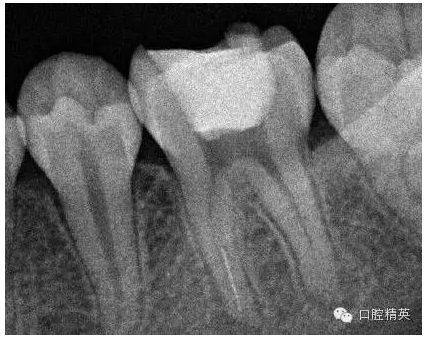

3,術(shù)前左下6近中根管斷針X-P,斷針長(zhǎng)度約4MM,根尖慢性炎癥影像。。。